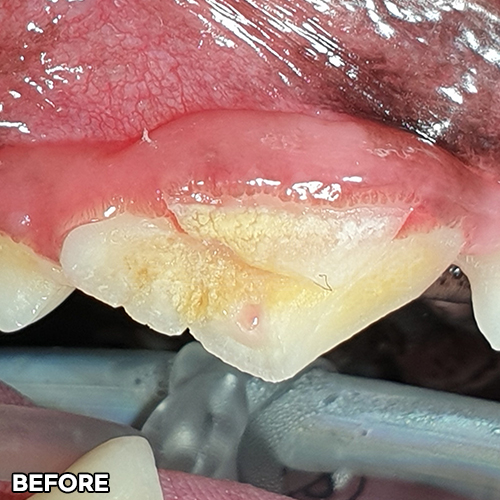

[강아지어금니파절, 치아흡수, 치수괴사, 치근단농양, 치근단공개방....! 편측절제(Hemisection)]

샘플